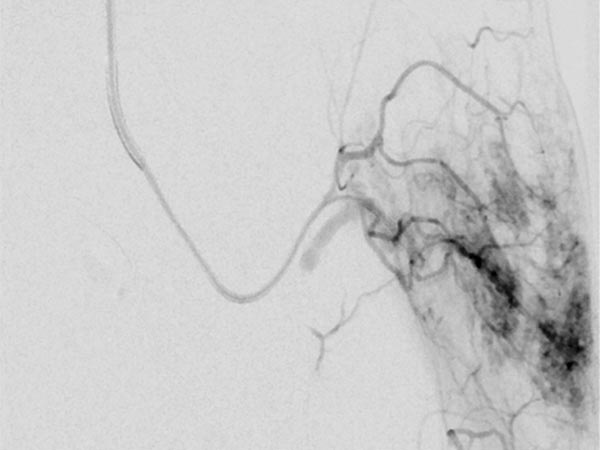

Nachdem am Ende des 3. Lebensjahres immer noch keine Rückbildungstendenz des Tumors sichtbar war, wurde nach einer Biopsie eine Embolisation zur Induktion einer Involution durchgeführt. Die Digitale Subtraktionsangiographie (DSA) zeigt einen Mikrokatheter superselektiv in einem Tumorgefäß. Der Tumor ist stark perfundiert und lobuliert, sehr früher venöser Abstrom, typisch für ein NICH.

Partikelembolisation mit sphärischen Partikeln der Größe 250 Mikrometer über den superselektiv in den Tumor eingeführten Mikrokatheter.

Weitere Tumorgefäße mit blush-artigem, diffusem Enhancement, typisch für Gefäßtumor/NICH. All diese Gefäße müssen selektiv embolisiert werden um eine Involution zu induzieren.